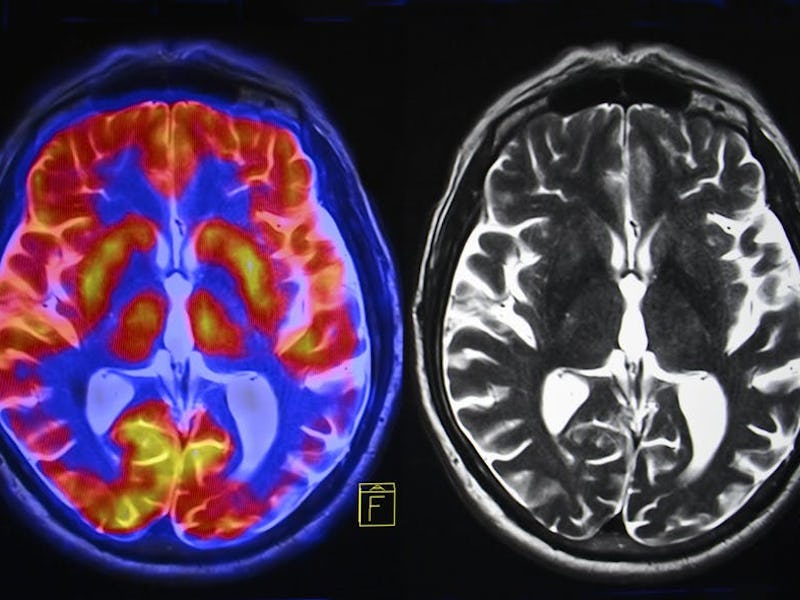

The brain’s hippocampus is a critical brain region for learning and memory and is particularly vulnerable to such insults. Studies in humans have shown that inflammation can adversely affect brain systems linked to motivation and mental agility.

There is also evidence of chronic stress effects on hormones in the brain, including cortisol and corticotropin-releasing factor (CRF). High, prolonged levels of cortisol have been associated with mood disorders as well as shrinkage of the hippocampus. It can also cause many physical problems, including irregular menstrual cycles.

There are many reasons for this, and they can be linked to changes in the brain. The reduced hippocampus that persistent exposure to stress hormones and ongoing inflammation can cause is more commonly seen in depressed patients than in healthy people.